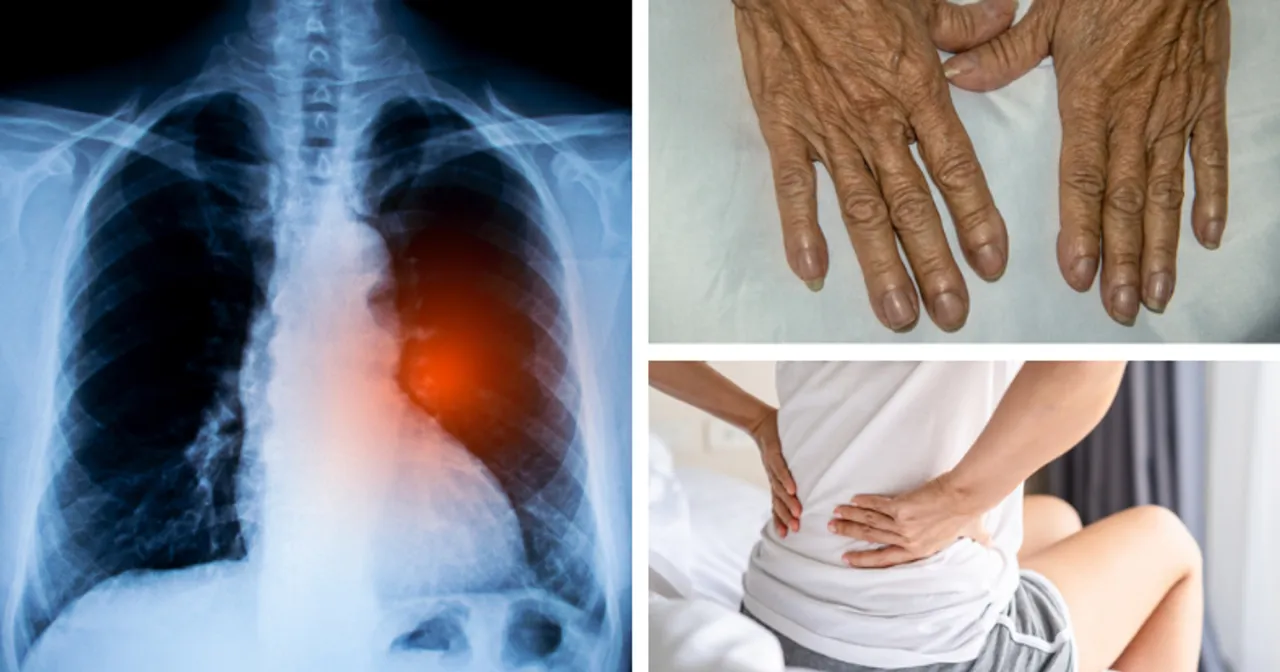

- Do najczęstszych schorzeń leczonych przez torakochirurgów należą nowotwory (zwłaszcza rak płuca), odma opłucnowa, ropniaki, urazy klatki piersiowej oraz wady wrodzone.

Chirurgia klatki piersiowej, znana również jako torakochirurgia, to wyspecjalizowana dziedzina medycyny, która koncentruje się na diagnostyce i leczeniu operacyjnym chorób, wad wrodzonych oraz urazów występujących w obrębie klatki piersiowej. Jej zakres działania jest szeroki, obejmując takie narządy jak płuca, opłucna, tchawica, oskrzela, przełyk, przepona oraz struktury śródpiersia. Kluczowe jest jednak zrozumienie, że torakochirurgia wyraźnie wyłącza leczenie serca, które jest domeną innej, choć pokrewnej, specjalizacji.

Głównym obszarem zainteresowania torakochirurgii są płuca i opłucna. To właśnie schorzenia tych narządów dominują w praktyce torakochirurgicznej, zwłaszcza nowotwory płuc, które stanowią jedno z największych wyzwań współczesnej medycyny. Opłucna, czyli błona otaczająca płuca, również bywa miejscem patologii wymagających interwencji chirurgicznej, takich jak odma opłucnowa czy ropniaki. Moje doświadczenie pokazuje, że precyzyjna diagnostyka i szybka decyzja o zabiegu w tych przypadkach mogą uratować życie.

Torakochirurg zajmuje się również śródpiersiem i przełykiem. Śródpiersie to przestrzeń między płucami, w której znajdują się ważne narządy, takie jak tchawica, duże naczynia krwionośne, grasica i węzły chłonne. Nowotwory śródpiersia, choć rzadsze niż nowotwory płuc, wymagają często skomplikowanych operacji. Przełyk, będący częścią przewodu pokarmowego, również podlega leczeniu torakochirurgicznemu w przypadku zwężeń, uchyłków czy nowotworów. Operacje w tych okolicach są często bardzo wymagające ze względu na bliskość wielu życiowo ważnych struktur.

Do zadań torakochirurga należy także leczenie schorzeń dotyczących przepony, tchawicy, oskrzeli oraz ściany klatki piersiowej. Przepona, kluczowy mięsień oddechowy, może być dotknięta przepuklinami, które wymagają chirurgicznej korekcji. Tchawica i oskrzela, jako drogi oddechowe, bywają miejscem zwężeń, guzów czy urazów. Co więcej, torakochirurdzy zajmują się korekcją wad wrodzonych i nabytych ściany klatki piersiowej, takich jak klatka lejkowata czy kurza, a także leczeniem skomplikowanych urazów żeber i mostka. To pokazuje, jak wszechstronna jest ta specjalizacja.

Nie da się ukryć, że choroby nowotworowe stanowią lwią część wyzwań, z jakimi mierzą się torakochirurdzy. Rak płuca jest niestety najczęstszym nowotworem, który wymaga interwencji chirurgicznej w obrębie klatki piersiowej. Moja praktyka pokazuje, że wczesne wykrycie i radykalne leczenie operacyjne dają pacjentom największe szanse na wyleczenie. Poza rakiem płuca, torakochirurdzy zajmują się również nowotworami przełyku, śródpiersia i opłucnej, a także usuwaniem przerzutów innych nowotworów do płuc, co jest często kluczowym elementem leczenia onkologicznego.